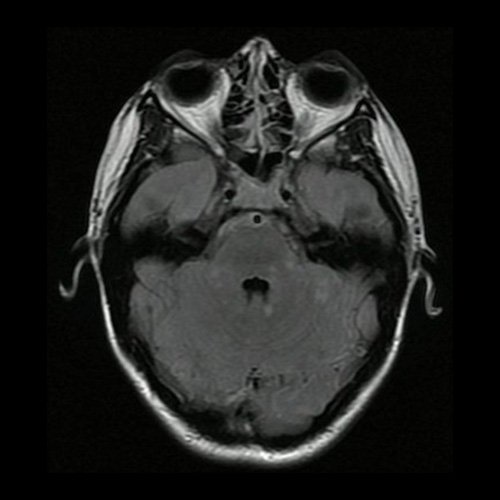

Día 2: RMI de cráneo ( T2 Flair – corte axial). Lesiones hiperintensas nodulares sólidas en protuberancia, pedúnculos cerebelosos y hemisferios cerebelosos.

La RMI muestra lesiones hiperintensas en T2 y FLAIR a nivel periventricular y subcortical, incluido el cuerpo calloso y el centro semioval, así como en la sustancia gris, incluida la corteza, los ganglios basales y el tálamo. Las lesiones infratentoriales en el tronco encefálico, el cerebelo y la médula espinal son comunes. Suelen tener realce con gadolinio. Difusión restringida.